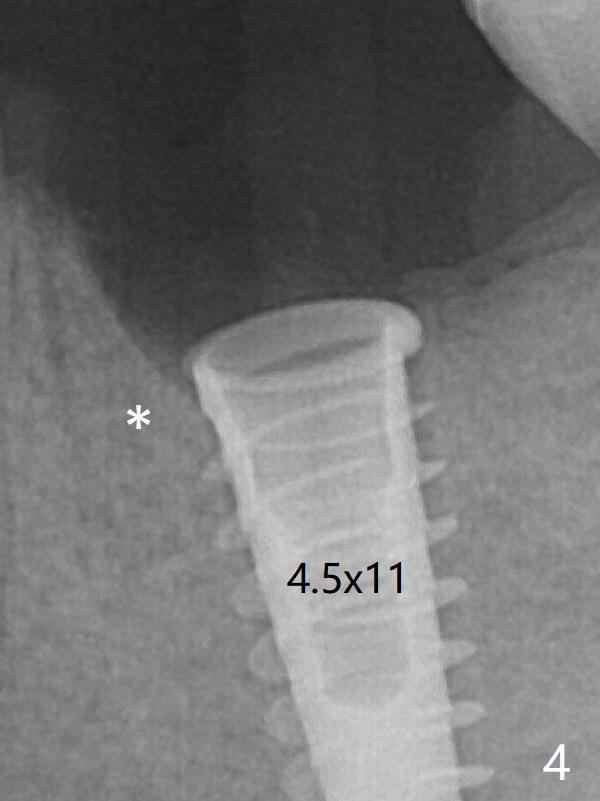

Due to the narrow ridge, a 4.5x11 mm implant is placed (Fig.4); before as well as after placement of a 6x4(3) mm abutment, the mesial socket (*) is filled with Vera graft and autogenous bone as well as collagen plug.  Following suturing, periodontal dressing is applied to the wound.  There is no apparent bone loss 7 months postop (Fig.6 (BW: bitewing)) or 14 months post cementation (Fig.7).  In fact the abutment has been incompletely seated, which may be related to #13 failure.